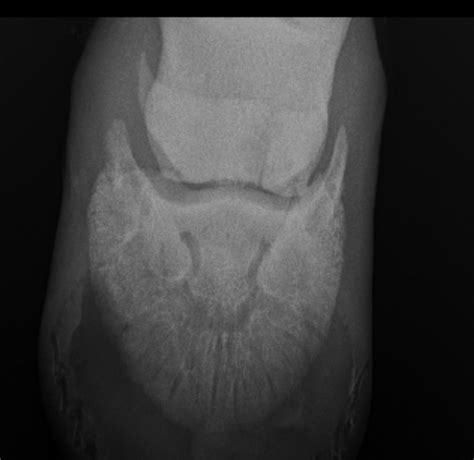

X-ray Imaging Primary scan to identify major breaks or displacement.

MRI or CT Scan Used for occult fractures that are hidden on standard X-rays.